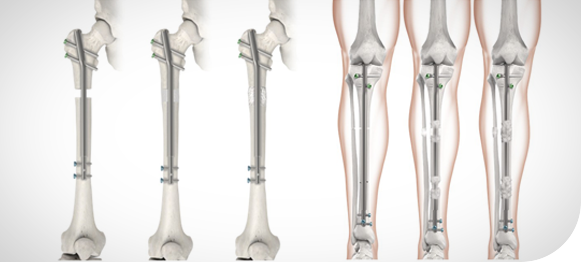

Know MoreStature Lengthening

Stature lengthening is a specialized procedure designed to increase limb length or correct limb length discrepancies. It is performed using advanced orthopedic techniques that gradually promote new bone growth.